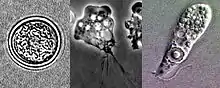

| Lifecycle stages of Naegleria fowleri: flagellate, trophozoite and cyst (seen from upper left to lower left to right) | |

Naegleria fowleri is a thermophilic, free-living amoeba. It is found in warm and hot freshwater ponds, lakes and rivers, and in the very warm water of hot springs.[15] As the water temperature rises, its numbers increase. The amoeba was identified in the 1960s in Australia but appears to have evolved in the United States.[16] N. fowleri occurs in three forms – as a cyst, a trophozoite (ameboid), and a biflagellate. It does not form a cyst in human tissue, where only the amoeboid trophozoite stage exists. The flagellate form can exist in the cerebrospinal fluid.

The cyst form is the storage-state of this amoeba. It is spherical and about 7–15 µm in diameter. It is smooth, having a single-layered wall with a single nucleus. A cyst is a life-capsule resistant to adverse environmental-conditions. Trophozoites encyst due to unfavorable conditions. Factors that induce cyst formation include a lack of food, overcrowding, desiccation, accumulation of waste products, and cold temperatures.[17] When conditions improve, the amoeba can escape through the pore, or ostiole, seen in the middle of the cyst. N. fowleri has been found to encyst at temperatures below 10 °C (50 °F).[18]

Trophozoite stage

The trophozoite is the feeding, dividing, and infective stage for humans. The trophozoite attaches to olfactory epithelium, where it follows the olfactory cell axon through the cribriform plate (in the nasal cavity) to the brain. This reproductive stage of the protozoan organism, which transforms near 25 °C (77 °F) and grows best around 42 °C (106.7 °F), proliferates by binary fission. The trophozoites are characterized by a nucleus and a surrounding halo. They travel by pseudopodia, which means that they extend parts of their body's cell membrane (the pseudopods) and then fill them with protoplasm to force locomotion. The pseudopods form at different points along the cell, thus allowing the trophozoite to change directions. In their free-living state, trophozoites feed on bacteria. In tissues, it appears they phagocytize (consume by enclosing and then digesting prey) red blood cells and destroy tissue by releasing cytolytic substances.[17]

Flagellate

The flagellate is pear-shaped and biflagellate: this means that it has two flagella. This stage can be inhaled into the nasal cavity during swimming or diving. This biflagellate form occurs when trophozoites are exposed to a change in ionic concentration, such as placement in distilled water. The flagellate form does not exist in human tissue, but can exist in the cerebrospinal fluid. Once inside the nasal cavity, the flagellated form transforms into a trophozoite. The transformation of flagellate to trophozoite occurs within a few hours.[17]